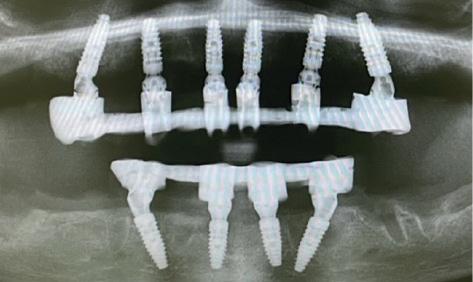

CASE STUDY

Guided implant approach for reproducible results, page 28

1. Adaptable to different guided surgery protocols: piloted, semi-guided or fully guided.

2. No friction between drills and guide sleeve, no overheating and no release of particles.

3. No specific drills and a very small surgical box.

4. Full control of drilling depth.

5. Your conventional driver-guided drilling sequence.